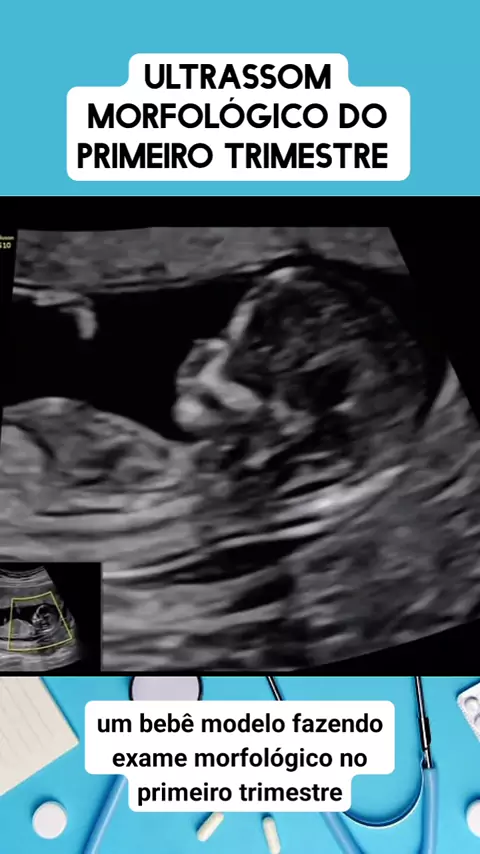

ultrassom morfol贸gica do primeiro trimestre #medico #medicina #Sa煤de #viraliza